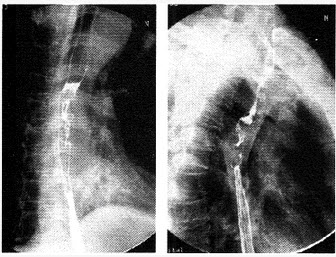

�����У�58�ꡣ��������2�����࣬X��ͼ�����£����п��ܵ�����ǣ���